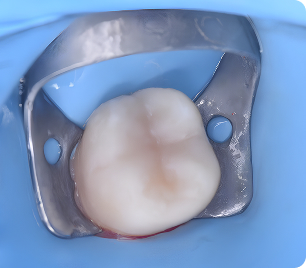

Специализация: лечение кариеса, пульпита и периодонтита временных зубов